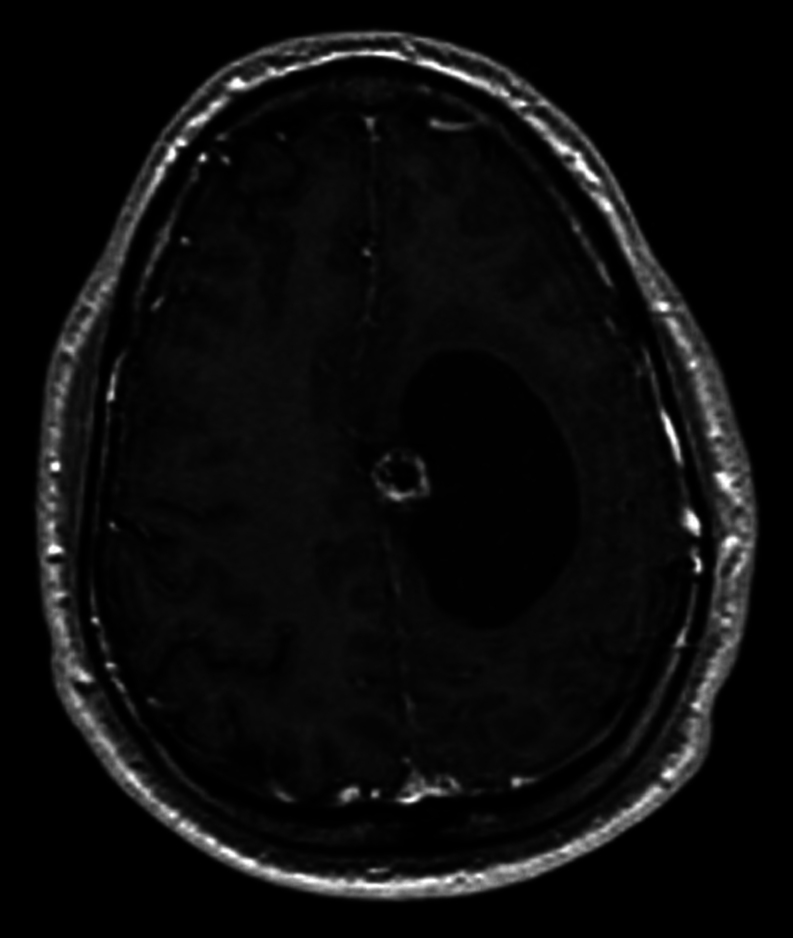

摘要:以脑转移为首发临床表现的甲状腺乳头状癌(PTC)并不多见,而海绵状血管瘤则是常见的脑畸形。我们报告了一例 36 岁男性的病例,他的脑部病变在磁共振成像上模仿了海绵状血管瘤。患者接受了伽玛刀放射外科手术,但 6 个月后出现了神经症状,复查脑部磁共振成像发现肿块明显增大。患者接受了神经外科手术,病变组织学检查显示为甲状腺转移癌。随后进行的PET-CT和颈部超声检查显示,患者右叶结节和同侧淋巴结的存在一致,超声特征均怀疑为恶性肿瘤。患者接受了甲状腺全切除术,并进行了颈部中央和右外侧清扫术,组织学检查证实患者为甲状腺内多灶性 PTC,并伴有淋巴结转移。术后使用了放射性碘,治疗后全身扫描发现甲状腺床内有局灶性摄取,无远处转移或脑残留。确诊两年后,患者健康状况良好,并接受了临床和影像学随访:学习要点:脑海绵状血管瘤是常见的脑血管畸形,通常通过核磁共振成像诊断。尽管核磁共振成像的准确率很高,但该检查并不具有病理诊断性,也不能排除误诊的可能。PTC 的脑转移非常罕见,但也可能与海绵状血管瘤相似。因此,应始终考虑鉴别诊断。

Summary: Brain metastases as the first clinical presentation of a papillary thyroid carcinoma (PTC) are exceptional, while cavernous angiomas are common cerebral malformations. We report the case of a 36-year-old male with an incidental brain lesion mimicking a cavernous angioma on MRI. Gamma knife radiosurgery was performed, but after 6 months, the patient developed neurological symptoms, and a repeat brain MRI revealed a significant increase in the mass. The patient underwent neurosurgery, and the histological examination of the lesion revealed metastatic carcinoma of thyroid origin. PET-CT and neck ultrasound, subsequently performed, were concordant for the presence of a right lobe nodule and ipsilateral lymph nodes, both with ultrasound features suspicious of malignancy. Total thyroidectomy with central and right lateral neck dissection was performed, and histology confirmed an intrathyroidal multifocal PTC with lymph node metastases. Postoperative radioiodine was administered, and focal uptake within the thyroid bed, without distant metastases or brain remnants, was found on the post-therapeutic whole-body scan. At 2 years from diagnosis, the patient is in good health and undergoes clinical and imaging follow-up.

Learning points: Brain cavernous angiomas are common cerebral vascular malformations that are usually diagnosed by MRI. Despite the high accuracy of MRI, the exam is not pathognomonic, and misdiagnosis cannot be excluded. Brain metastases from PTC are very rare; however, they can mimic a cavernous angioma. Therefore, the differential diagnosis should always be considered.